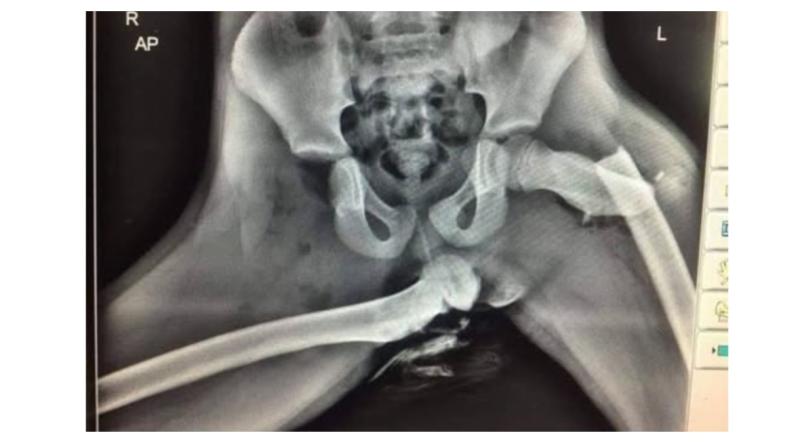

In a post shared to social media, Kilkenny gardaí showed an image shared with them by a Welsh police officer involved in casualty reduction, they said: "It's not a new image but never gets old. It's an Xray of a passenger in a car that had her feet up on the dashboard when a collision occurred."

They continued: "When a collision occurs, it's not the speed does the damage but slowing down. For safety systems to function properly in modern cars, you need to be seated correctly with your approved restraint functioning properly.

"You need to have your seatbelt on correctly, the seat angled correctly, your feet where they should be and all your passengers likewise."

The post concluded: "Save our Paramedics and Medical personnel from seeing sights like this. Save yourself from suffering them."